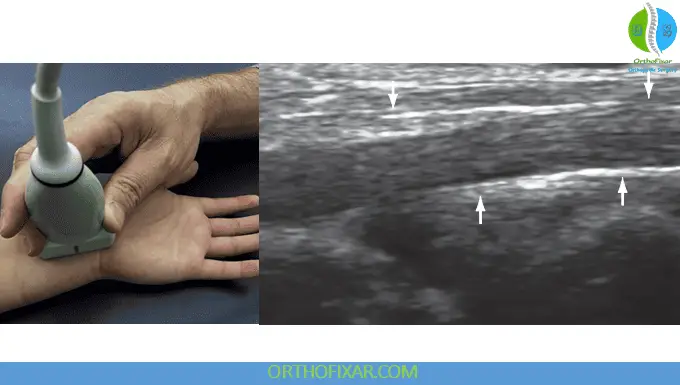

Long Axis Visualization: Rotating the transducer 90° provides long axis views where nerve fascicles are clearly delineated. This orientation facilitates identification of nerve compression, characterized by:

- Enlargement of nerve diameter at the compression site

- Proximal nerve swelling

- Echotexture changes indicating pathology